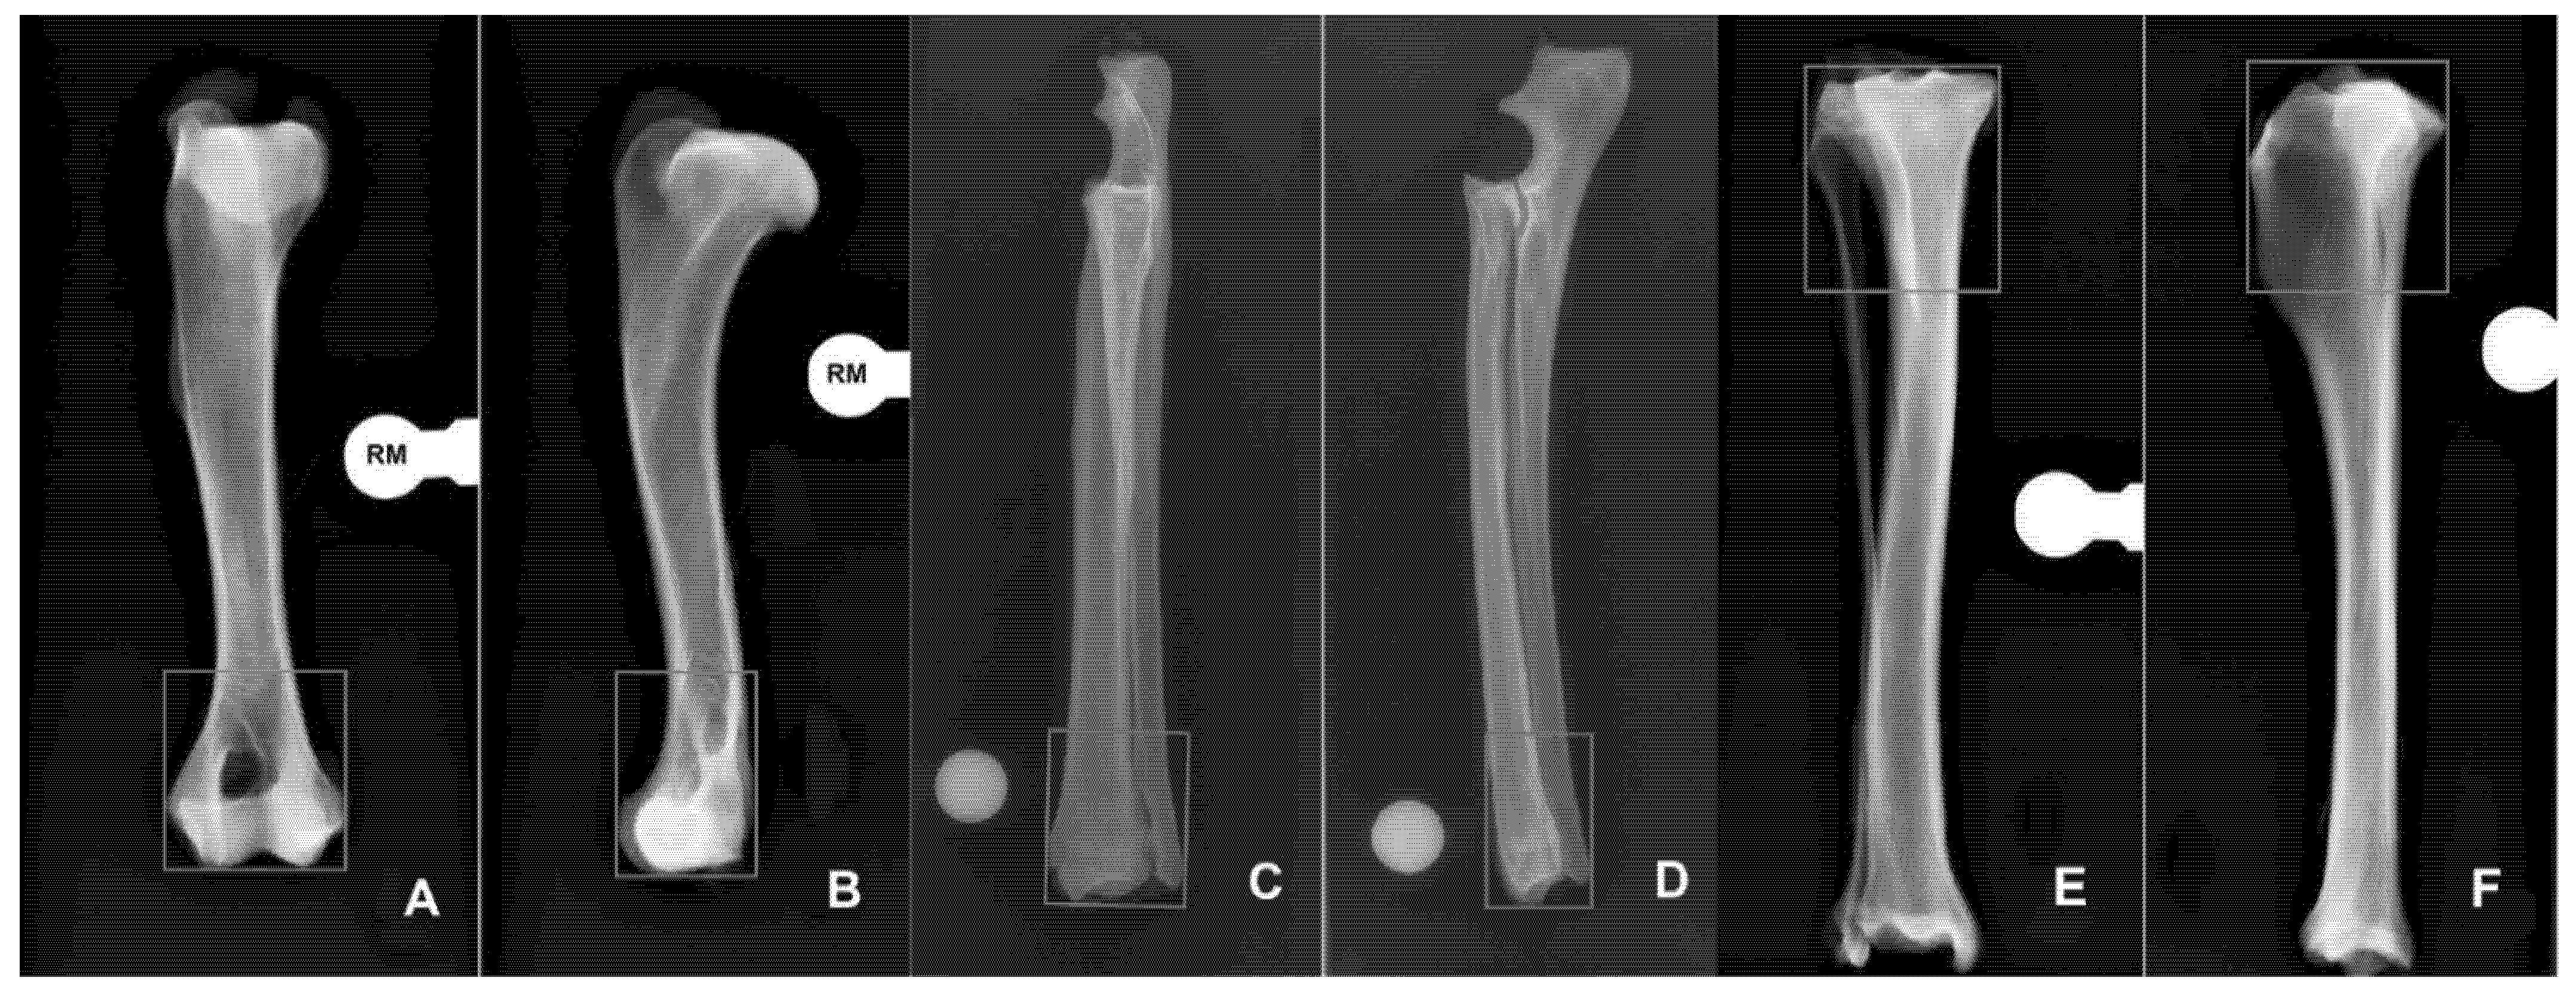

3.1. Humerus

3.2. Radius-Ulna

3.3. Tibia